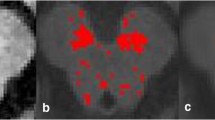

The SNc on NmMRI in each case was divided into four parts (1: right lateral, 2: right medial, 3: left medial, 4: left lateral) (Fig. 1). The contrast ratio of each part of the SNc was measured by defining the region of interest (ROI) on a liquid crystal display following the equation: SSNc−SSC/SSC, where SSNc is the signal intensity of the SNc, and SSC is the signal intensity of the SC. ROIs were placed in the four parts of the SNc in each one of the three specimens and strictly traced according to the margins of the anatomical regions. Each size of ROI was also evaluated. All images were analyzed by two experienced neuroradiologists (S.K and E.M) and the ROIs were reproducibly measured.

Measurement of NmMRI and myelin-stained sections. a Postmortem NmMRI of the midbrain (case 1: normal control). The SNc is clearly identified as band-like hypersignal areas in the posterior portion of the cerebral peduncle. Each side of the SNc is divided into medial and lateral parts, and therefore, the SNc is divided into four parts (1: right lateral, 2: right medial, 3: left medial, 4: left lateral). Bilateral SCs are also shown (dotted lines). b A myelin-stained (Klüver–Barrera stain) section corresponding to a (case 1). The SNc is divided into four similar parts. The number of neuromelanin-containing neurons was counted in each part of the SNc in all cases. Furthermore, to obtain density of the neuromelanin-containing neurons (number per square millimeter) in each part of the SNc, the number of neurons was divided by the ROI size in each part of the SNc

The SNc on myelin-stained (Klüver–Barrera stain) sections in each case was similarly divided into four parts (Fig. 1). The number of neuromelanin-containing neurons was counted manually in each part of the SNc under a light microscope in all cases. Furthermore, to obtain density of the neuromelanin-containing neurons (number per millimeter) in each part of the SNc, the number of neurons was divided by the ROI size in each part of the SNc.